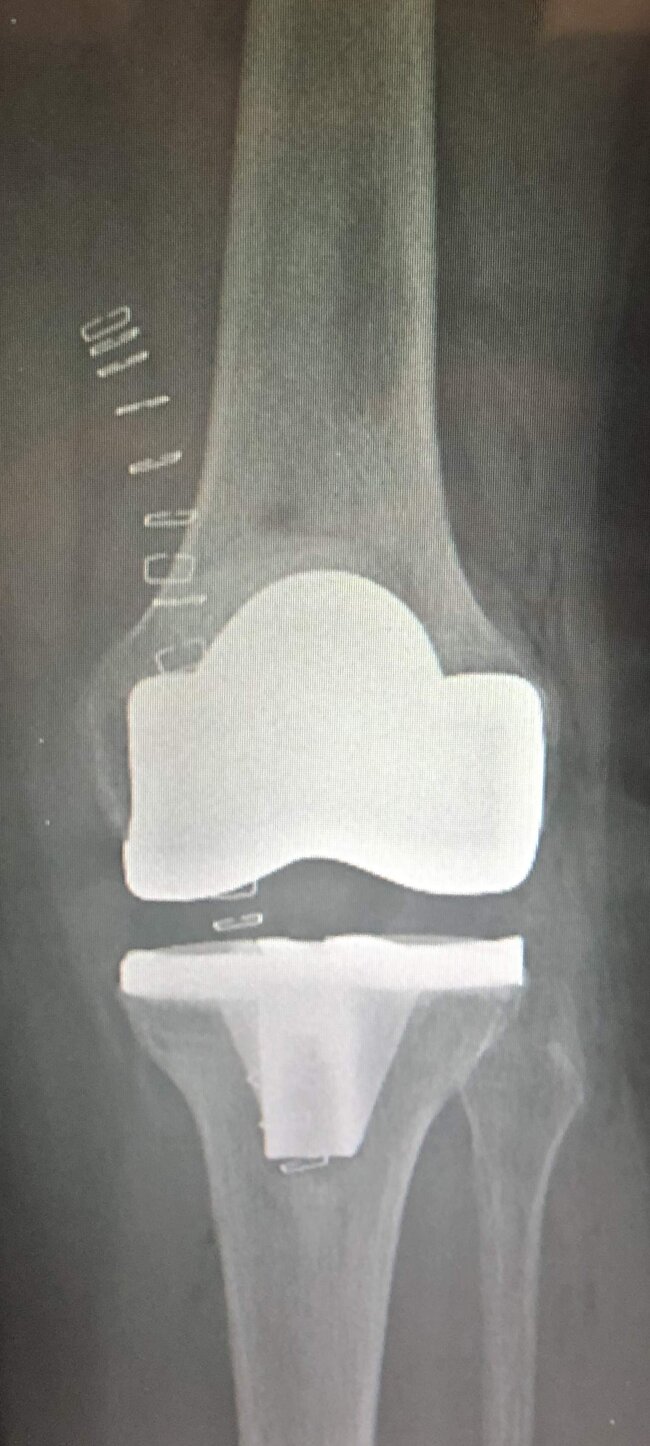

La protesi di ginocchio consiste in un rivestimento completo o parziale dell'articolazione, quindi ricoprendo sia la superficie articolare della tibia che quella del femore. A discrezione del chirurgo ed in base al caso specifico si può rivestire anche la rotula. Volendo semplificare la procedura di impianto di una protesi di ginocchio si possono individuare alcuni passaggi dell'intervento:- preparazione delle superfici ( si asportano i residui di cartilagine, esponendo l'osso sub-condrale in modo da avere una base di appoggio uniforme per la protesi )

-impianto delle componenti metalliche ( si impiantano due componenti metalliche articolari una per il femore e l'altra per la tibia, che costituiranno la nuova articolazione )

-posizionamento dell'inserto ( tra le due componenti metalliche del femore e della tibia viene posizionato un inserto in polietilene cioè una plastica ad alto peso molecolare, per curare la superficie di scorrimento ed ammortizzare i carichi, per sostituire la funzione dei menischi, l'inserto può essere fisso oppure mobile attorno ad un perno centrale )

-impianto della rotula ( si può decidere o meno in base al caso specifico se impiantare la protesi della rotula a seconda delle condizioni della cartilagine e della sintomatologia del paziente )

Intervento sicuro, elimina il dolore e corregge eventuali deformità della gamba. Dopo questo intervento potrai riprendere la tua vita di sempre e le normali attività senza dolore.